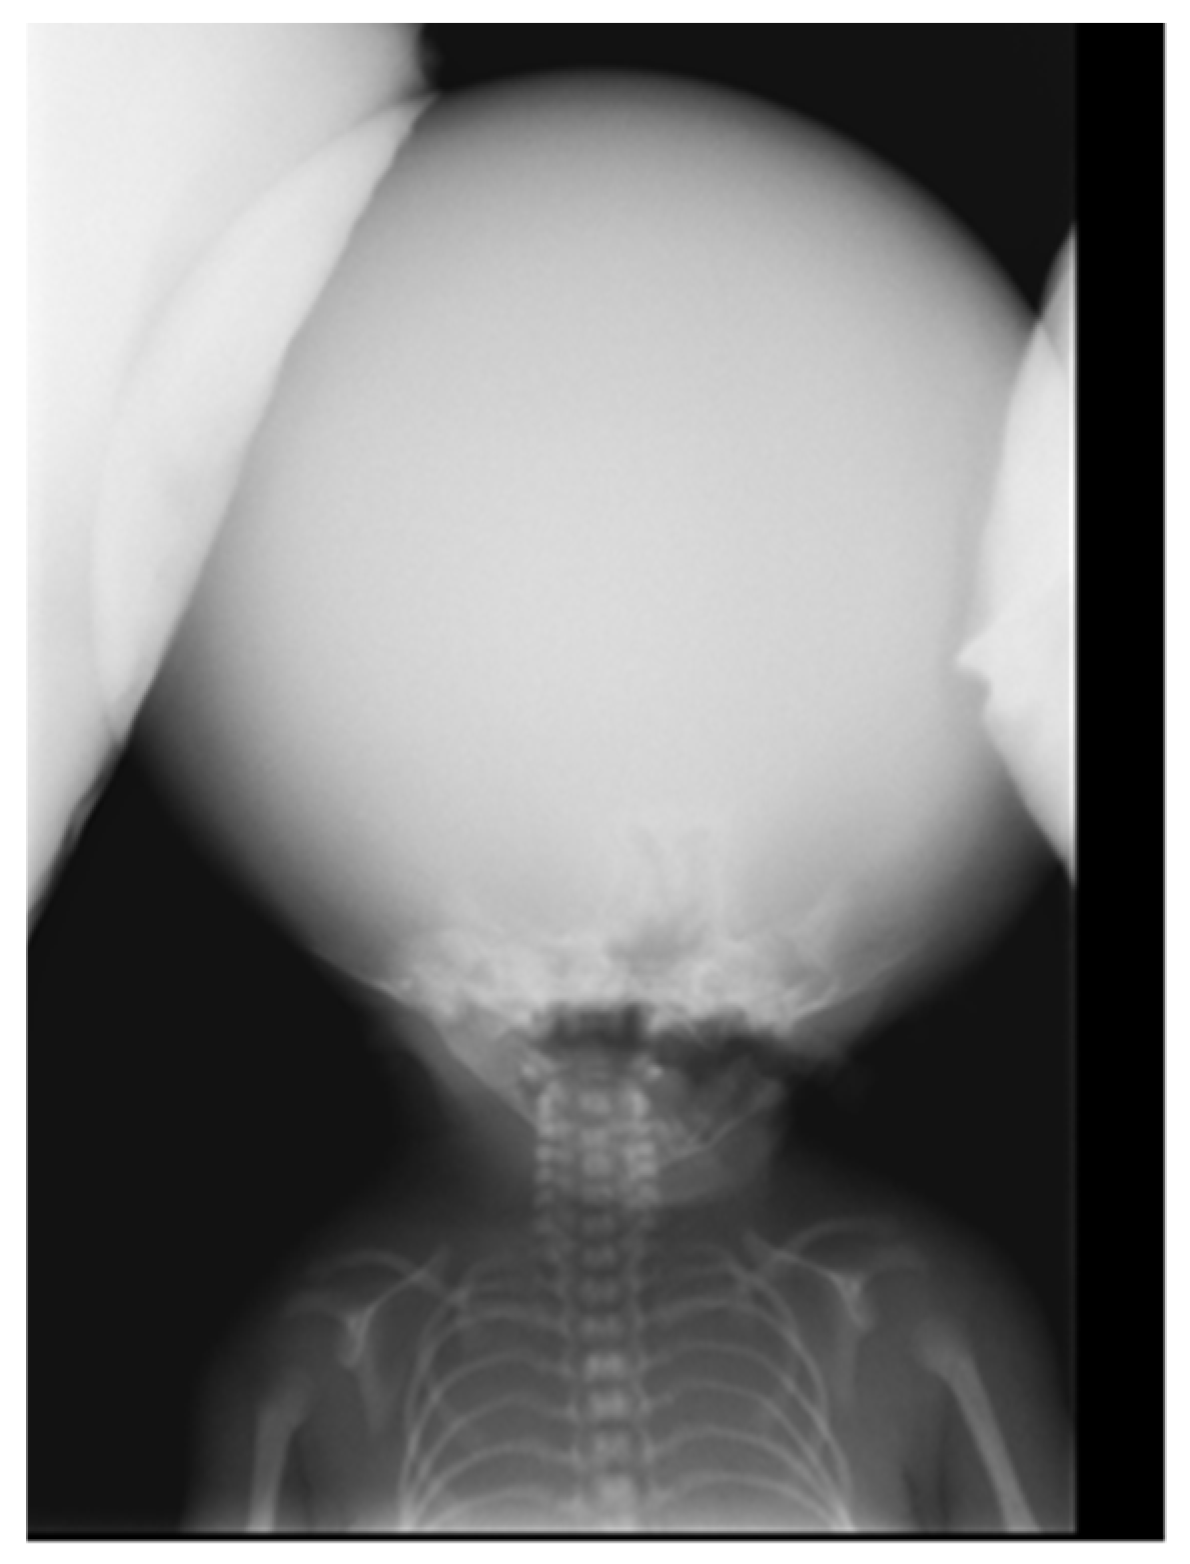

The X-ray image illustrates a significant skull expansion, confirming hydrocephalus, comprising macrocephaly, characterized by a disproportionately large head because of excessive cerebrospinal fluid accumulation inside the cranial cavity, along with a reduced bone density of the skull.